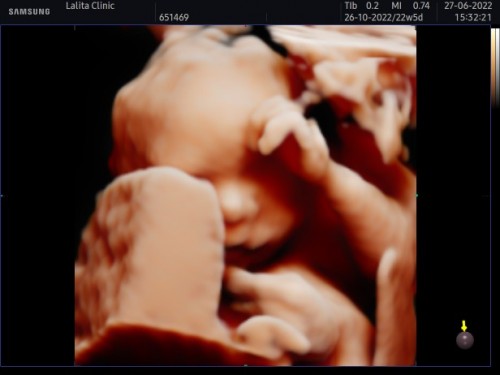

เห็นน้องชัดมากๆเลยค่ะ คุณแม่ซาว์ดที่ไหนราคาเท่าไรคะ ใช่คลีนิคลลิตาท้ายบ้านไหมคะ บ้านนี้ก็ทีมตุลาค่ะได้ลูกชาย รออายุครรภ์ครบ28สัปดาห์ ตั้งใจว่าจะไปซาว์ดอยู่เหมือนกัน อยากเห็นหน้าลูกชายล้าวว💕

ตอน22สัปดาห์คุณหมอบอกว่า501กรัมคะ..

ตอนไปซาวด์ 22w5d ค่า